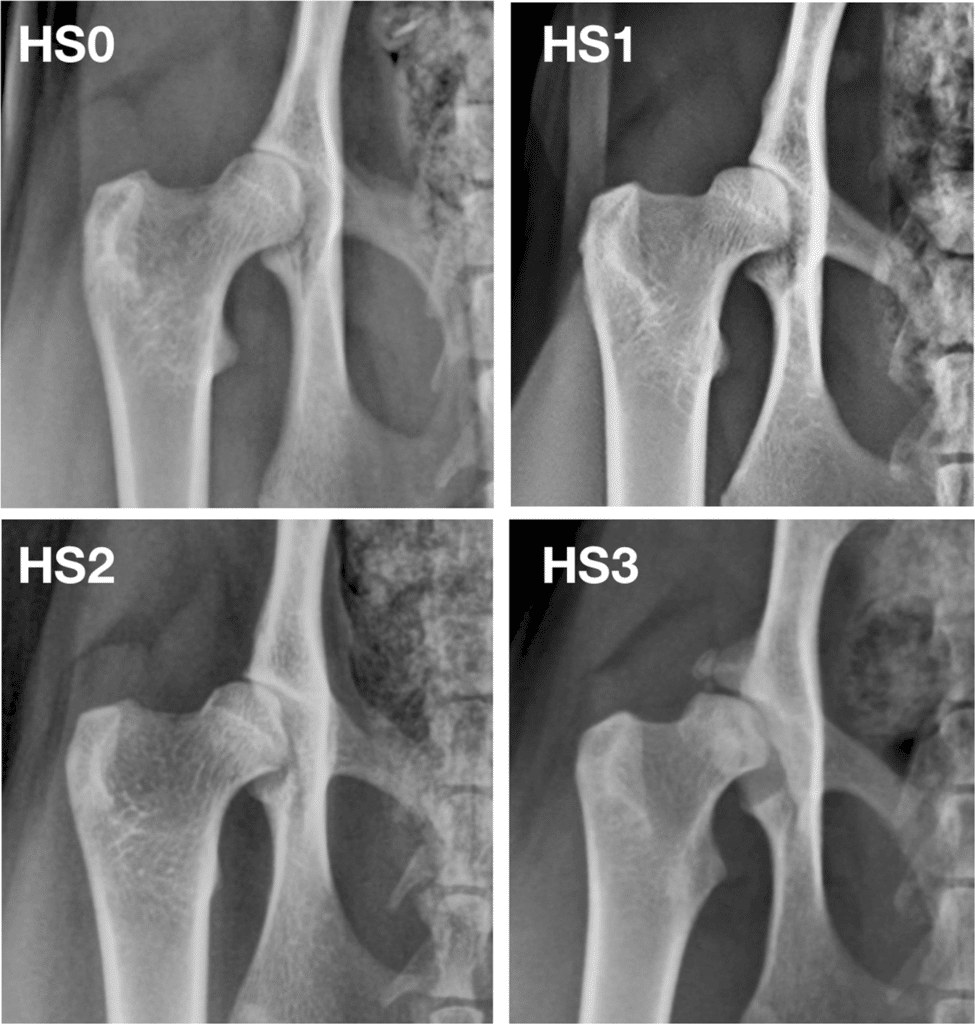

Below is an image taken from the PawPeds database, showing different grades of hip dysplasia. HS0 would be considered “Excellent” and HS3 is “severe”.